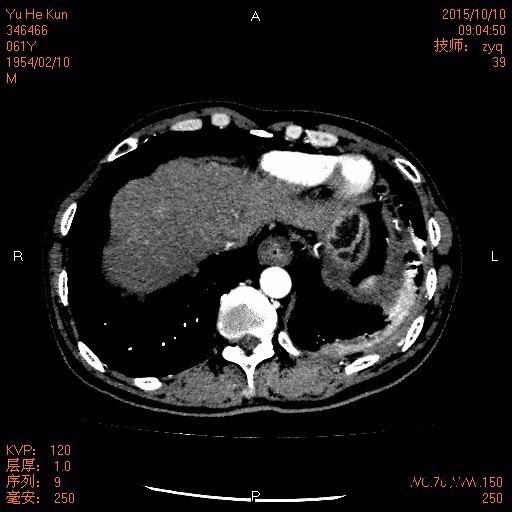

查体: T 36.8℃,BP 100/61mmHg,胸部可见既往胸腔镜检查愈合疤痕,双肺呼吸音清,双下肺呼吸音粗,未闻及干湿性罗音。 辅查: 1.胸膜活检:病变符合胸膜慢性炎伴间皮细胞增生。 2.胸水离心找癌细胞:见增生的间皮细胞,淋巴细胞,未见癌细胞 3.胸部,上腹部CT:胸膜间皮瘤”治疗后复查,1.双侧胸膜增厚较前增多、明显,左肺癌性淋巴管炎,纵隔多发淋巴结转移可能。2.左侧少量积液较前减少,现片示少量包裹性液-气胸,左肺下叶节段性压迫性肺不张。3.少量心包积液。4.符合贫血改变。